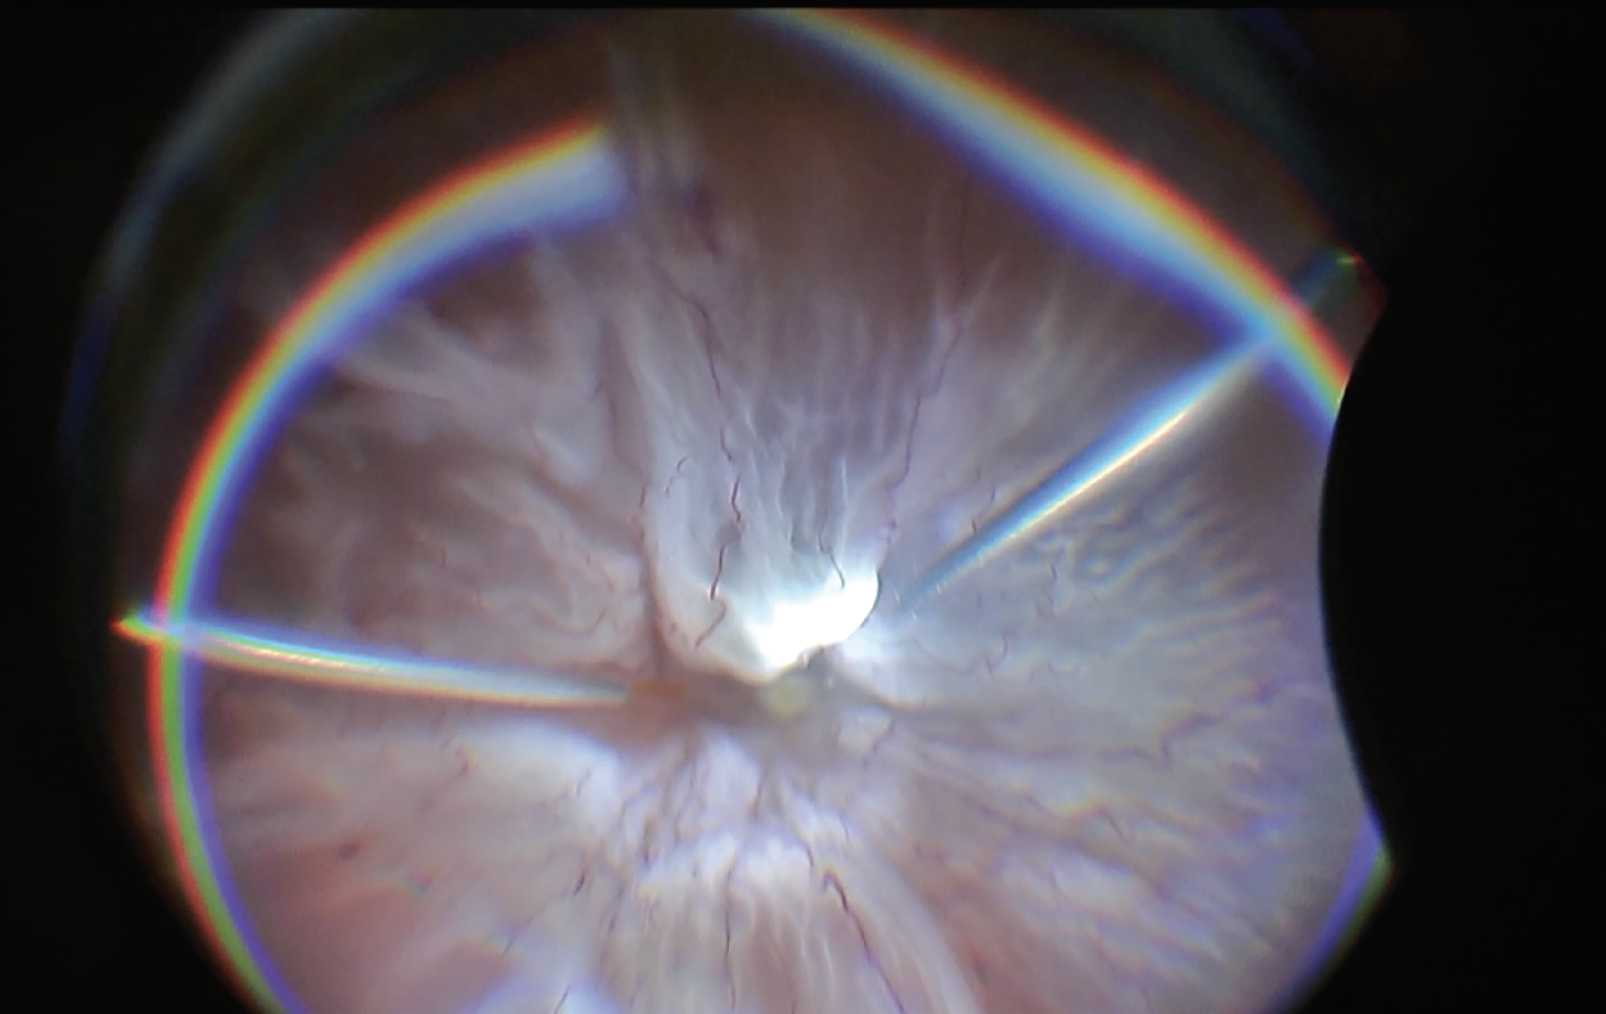

Figure 1. Preoperative view shows temporal retinal detachment with marked peripheral chorioretinal scarring, proliferative vitreoretinopathy, subretinal bands in the macula and a star fold with adjacent retinal break. Corresponding optical coherence tomography shows disorganized retinal laminations with tractional elevation. Figure 2. Postop, the scleral buckle appears to support the area of inferior traction. Previous areas of macular |